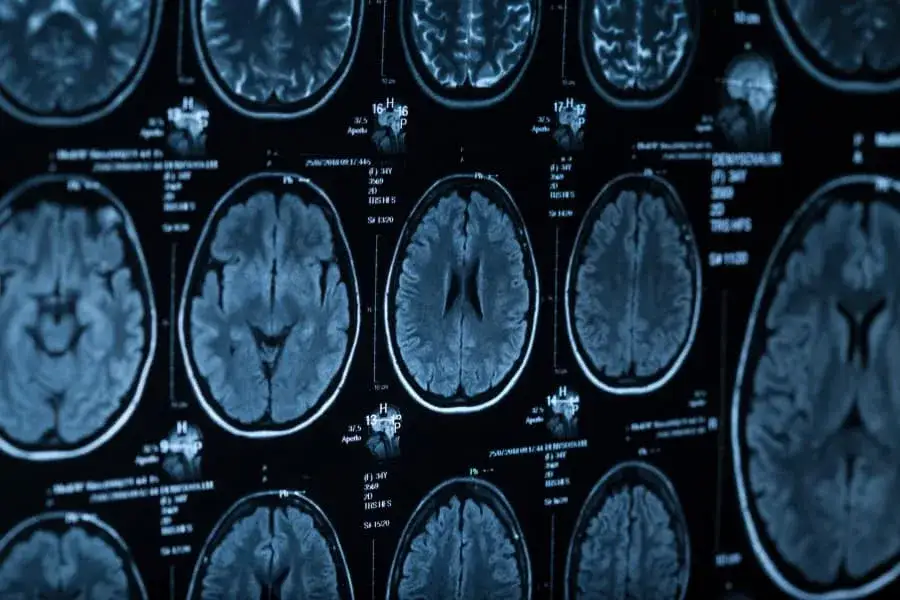

Czas trwania tomografii głowy jest kluczowym zagadnieniem dla pacjentów planujących to badanie. W zależności od tego, czy badanie jest przeprowadzane z kontrastem, czy bez, czas trwania procedury może się znacznie różnić. Standardowe skanowanie bez kontrastu trwa zazwyczaj od 10 do 15 minut, podczas gdy cała procedura z kontrastem, łącznie z przygotowaniem, może zająć od 30 do 60 minut.

Czas trwania tomografii głowy bez kontrastu jest zazwyczaj krótki, wynoszący od 10 do 15 minut. Warto jednak pamiętać, że w niektórych przypadkach, na przykład w sytuacji, gdy pacjent ma trudności z utrzymaniem nieruchomości, czas ten może się wydłużyć. Również zastosowanie różnego rodzaju sprzętu może wpływać na długość procedury.

Standardowe badanie tomografii głowy bez kontrastu trwa zazwyczaj od 10 do 15 minut. Warto jednak zauważyć, że czas ten może się różnić w zależności od indywidualnych okoliczności. Na przykład, jeśli potrzebne są dodatkowe zdjęcia lub jeśli pacjent ma trudności z pozostaniem w bezruchu, czas badania może być dłuższy.